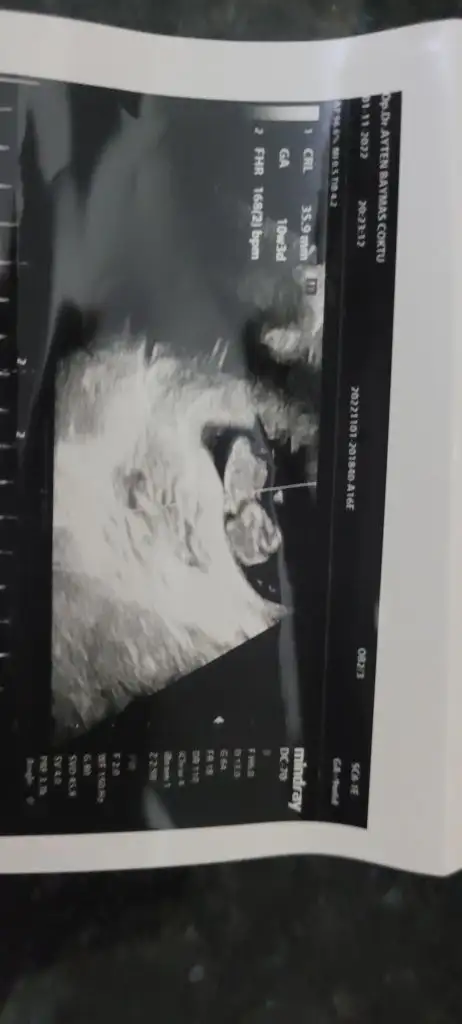

Kızlar banada tahmin yaparmisiniz 10+3 burda

Eklentiler

• 20221101_180411.webp

20221101_180411.webp

12,4 KB · Görüntüleme: 138

• 20221101_180406.webp

20221101_180406.webp

13,8 KB · Görüntüleme: 143